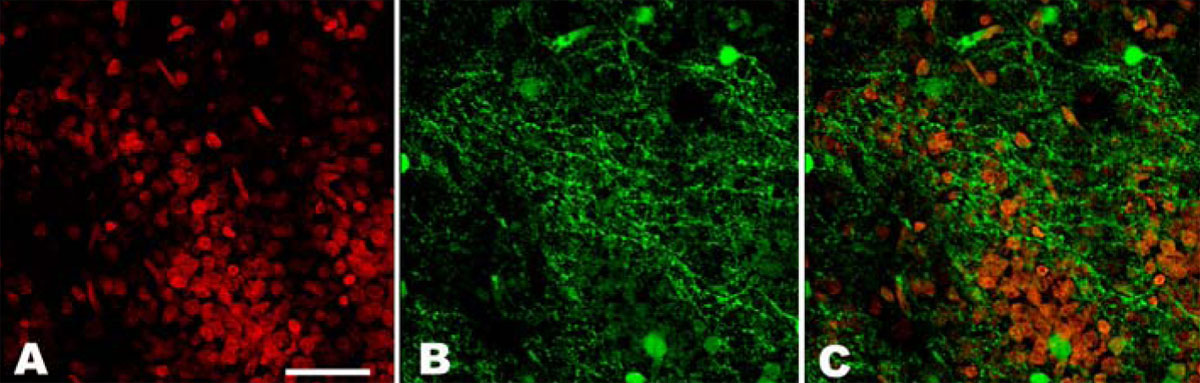

Figure 3. In vitro expression of cyclic guanosine monophosphate (cGMP) in the outer plexiform layer of a detached retina. Small pieces

of retina were incubated with IBMX (a non-specific PDE inhibitor) and the particulate guanylyl cyclase (pGC) stimulator atrial

natriuretic peptide (ANP). The expression of cGMP (cGMP: green color) in the retina was then analyzed by immunohistochemistry

and nuclei were counterstained with Hoechst 33342 (red). Following stimulation with ANP in the presence of IBMX, both the

detached and healthy retina showed cGMP-immunolabeling in the outer plexiform layer. Panel A shows the labeling of the outer

plexiform layer of a detached retina with Hoechst. Panel B shows the cGMP stain (green) of the outer plexiform layer probably

representing photoreceptor axons and dendrites. Panel C is a double staining exposure of the nuclei and cGMP. Scale bar represents

20 μm.